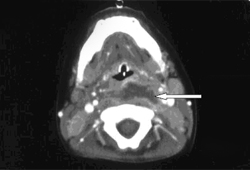

Radiological investigations are required to confirm diagnosis. The selected investigation depends on the degree of suspicion and access to the different imaging modalities, as well as the severity of the case. Nonetheless, a CT scan is the definitive investigation and will demonstrate a ring-enhancing lesion in the retropharyngeal tissues when performed with contrast.

[Figure caption and citation for the preceding image starts]: CT scan of neck demonstrating ring-enhancing lesionPhilpott CM, Selvadurai D, Banerjee AR. Paediatric retropharyngeal abscess. J Laryngol Otol. 2004;118:919-926 [Citation ends].